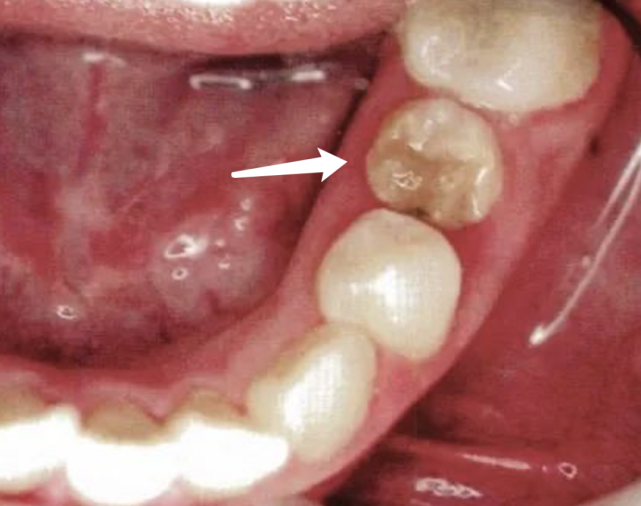

此时为保护恒牙胚,得把小乳牙给摘除(如下图所示,这也是为啥医生通常建议拍X线片的原因。)

炎症导致牙根吸收,根周骨质破坏,范围累及恒牙胚